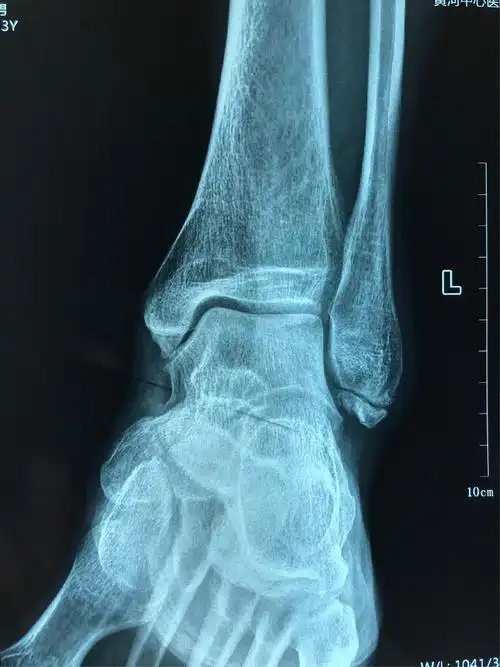

郑州市骨科医院足踝外科 王亚磊 左踝关节外侧副韧带损伤